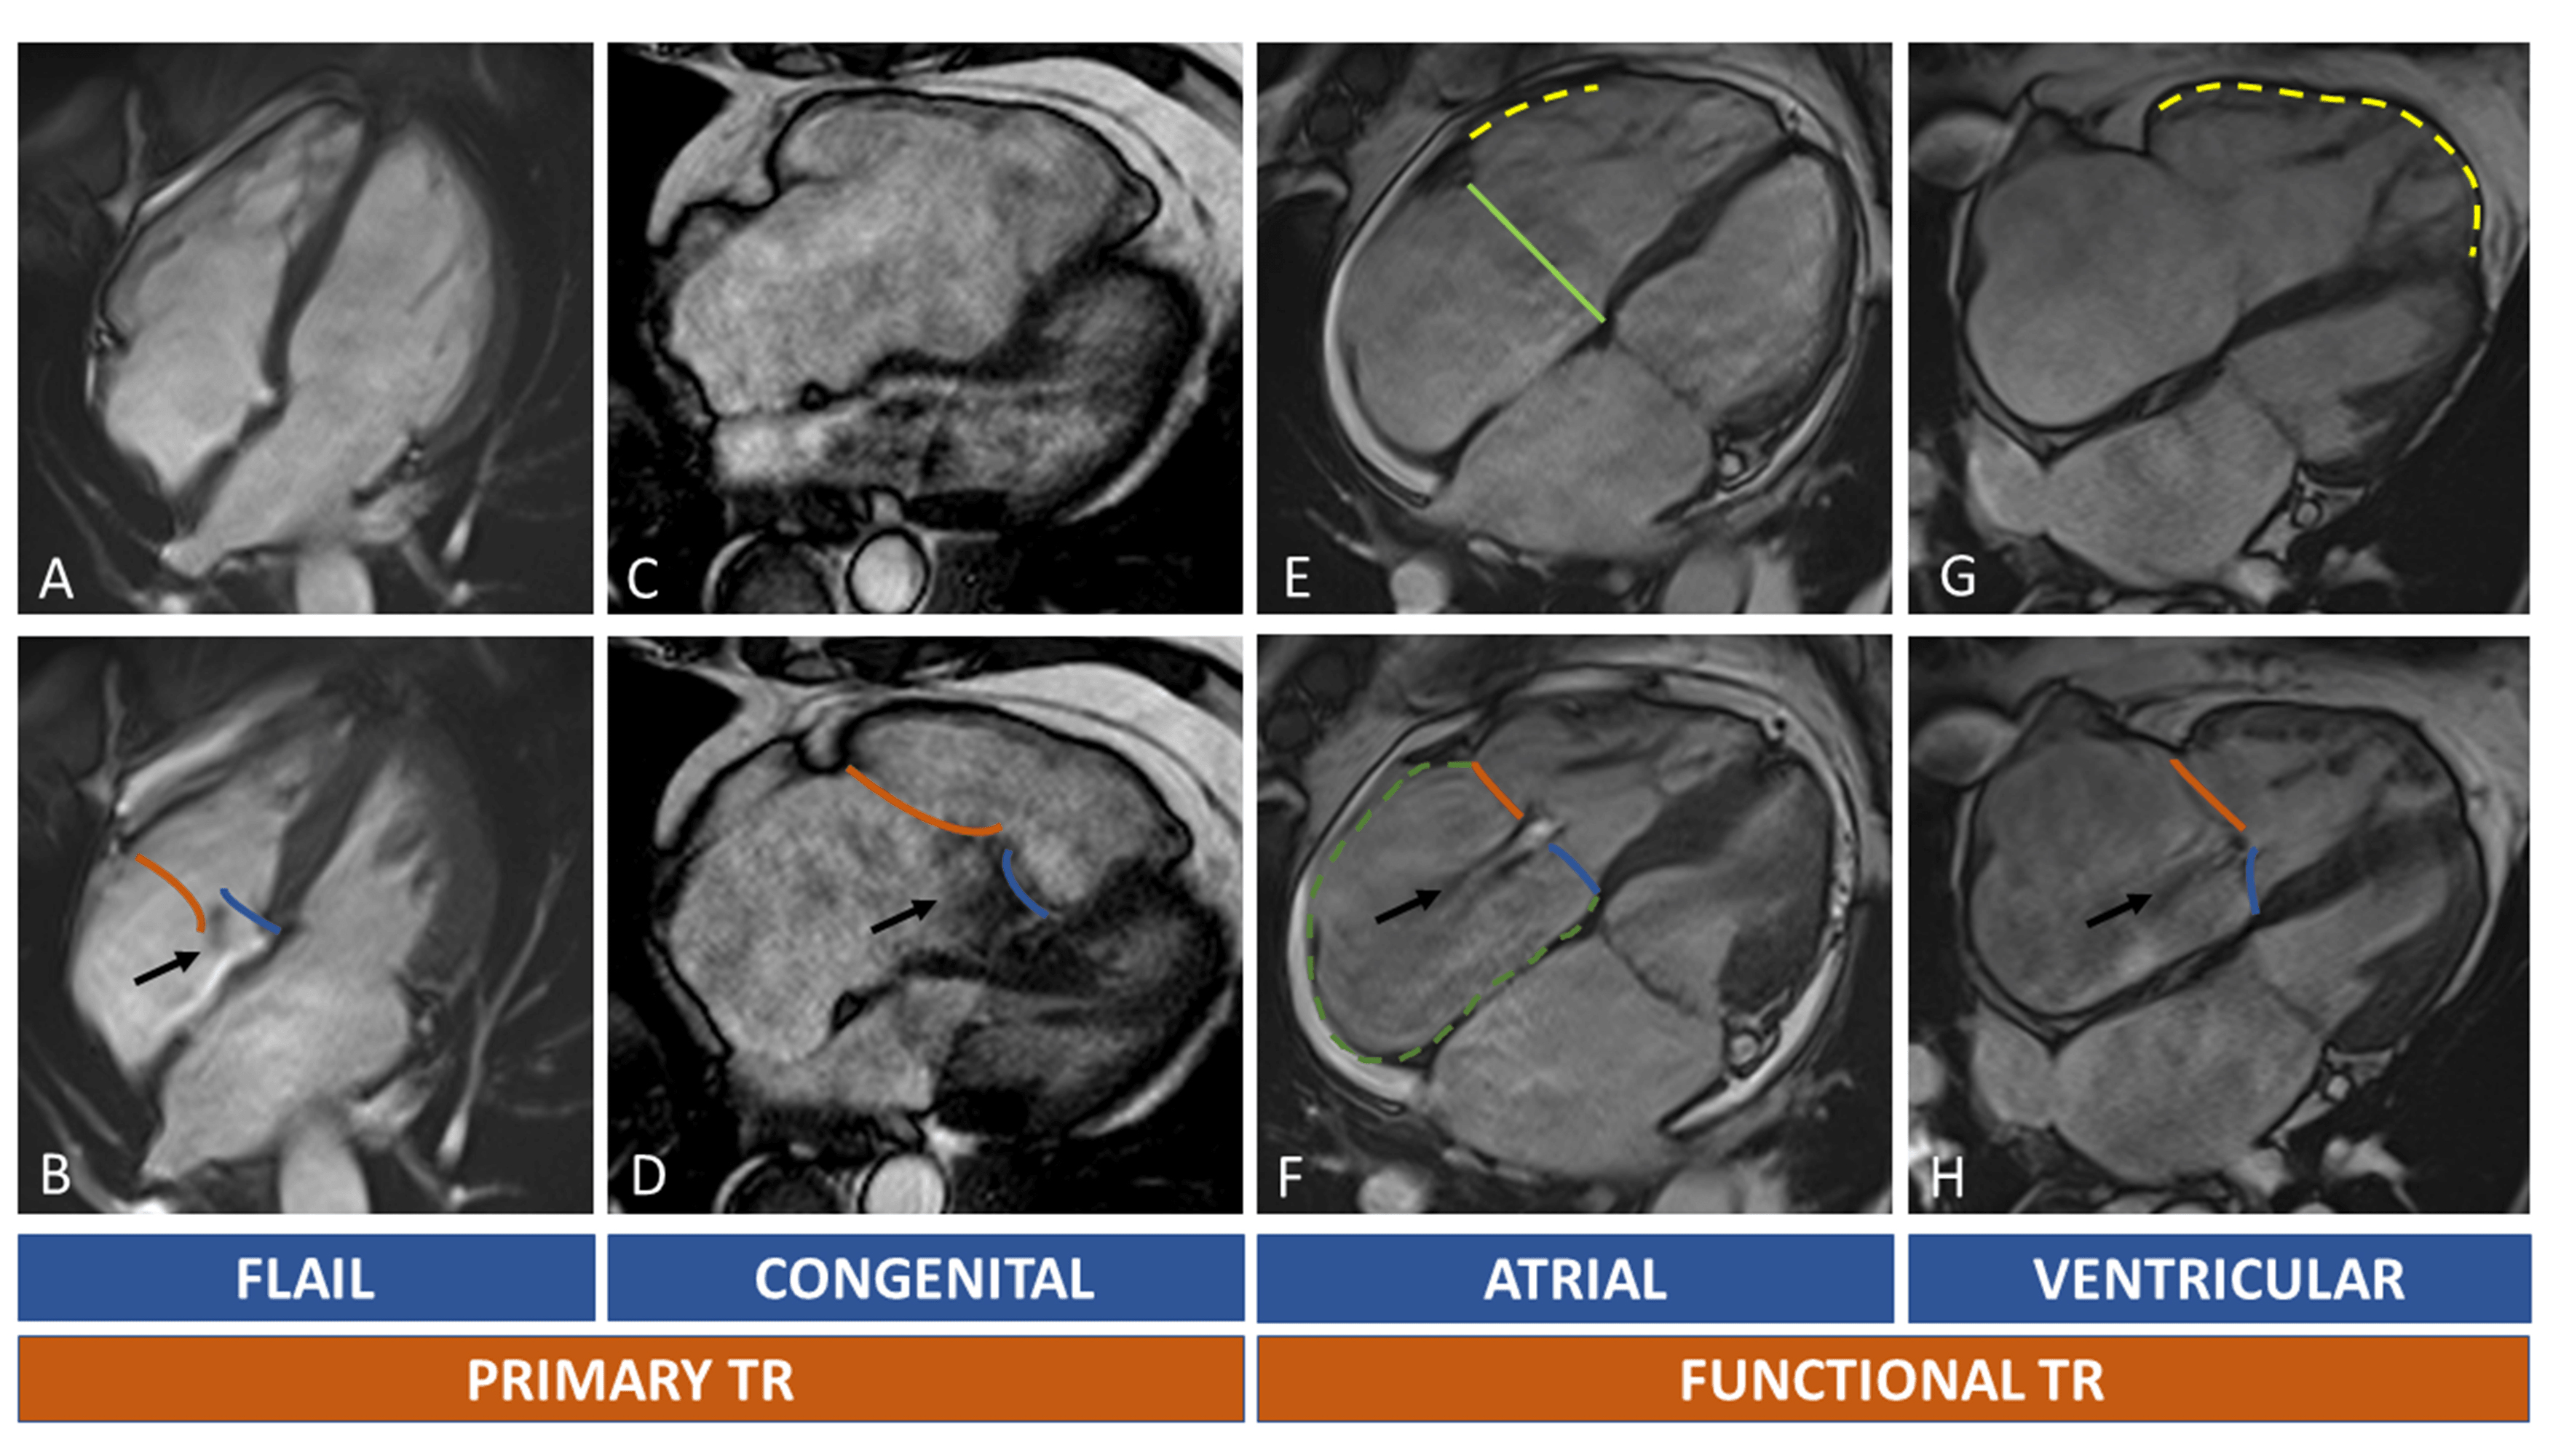

In primary TR, the RA or RV can be normal or mildly dilated during the first phases of the disease; however, as TR begets TR, in long-standing primary TR, signs of volume overload may develop, with RA, RV and TA enlargement. In secondary TR, the mechanism of regurgitation in mainly related to RA or RV dilatation without primary leaflet abnormalities (see Fig. 5).

Fig. 5.Tricuspid regurgitation and RH chambers remodelling. In (A–D) primary TR are shown. Upper row (A,C,E,G) show diastolic images, while the lower row (B,D,F,H) systolic images. The black arrow indicates the TR regurgitant jets. Orange line: anterior/posterior leaflet; blue line: septal leaflet. Light green line: septolateral diameter of TA in diastole. Dotted green line: right atrium. Dotted yellow lines: RV walls dilatation. Primary TR is caused by leaflets abnormalities. A case of flail leaflet is shown in (A,B): right chambers can be normal or mildly dilated because of recent onset of TR; in Ebstein anomaly (C,D) the TR is caused by displacement of septal leaflet (blue line) with distortion of normal right chamber anatomy. Secondary TR can be atrial or ventricular mediated. In atrial functional TR there’s a prevalent enlargement of the basal wall of RV ((E), yellow dotted line), of the TA (light green line) and RA ((F), green dotted line). In ventricular functional TR, the RV is globally enlarged ((G), yellow dotted line) causing leaflets tenting (H). Abbreviations: RA, right atrium; RH, right heart; RV, TA, tricuspid annulus; TR, tricuspid regurgitation; TV, tricuspid valve.